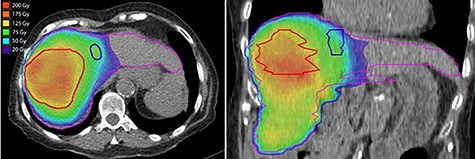

Post-treatment dosimetry done using the Bremsstrahlung liver SPECT image and the Sure Plan software demonstrated that the mean dose delivered to the main right liver lobe tumor (GTV) was 156 Gy. Ninety-five percent of the GTV received 108 Gy with a max dose of 213 Gy. The mean dose to the Segment IVA lesion was only 62 Gy, with 95% of the lesion receiving 36 Gy (Figs 8 and 9).

Axial and coronal views of the Y-90 dose distribution; the majority of the uptake is within the GTV with minor uptake in the Segment IVA lesion.

In this case report, we demonstrate that the post-Y-90 TARE dosimetry was predictive of treatment response. The main tumor which received a mean dose of 156 Gy showed a complete pathologic response, while the satellite nodule that was treated to a mean dose of 62 Gy showed only a partial response.

Since this was a procedure performed in preparation for a right lobectomy, a mean dose to the right liver lobe of 74 Gy was deemed acceptable. The left liver lobe was almost totally spared from any radiation with a mean dose of 25 Gy and 95% of the lobe receiving 3.5 Gy. These findings are in agreement with other published data indicating that delivering a dose higher that 100 Gy during Y-90 TARE leads to good tumor control [2]. The benefit of using Y-90 TARE to deliver an ablative radiation dose is that this treatment technique completely spares the surrounding extra hepatic organs from radiation. The use of dosimetry software brings important data for outcome analysis.